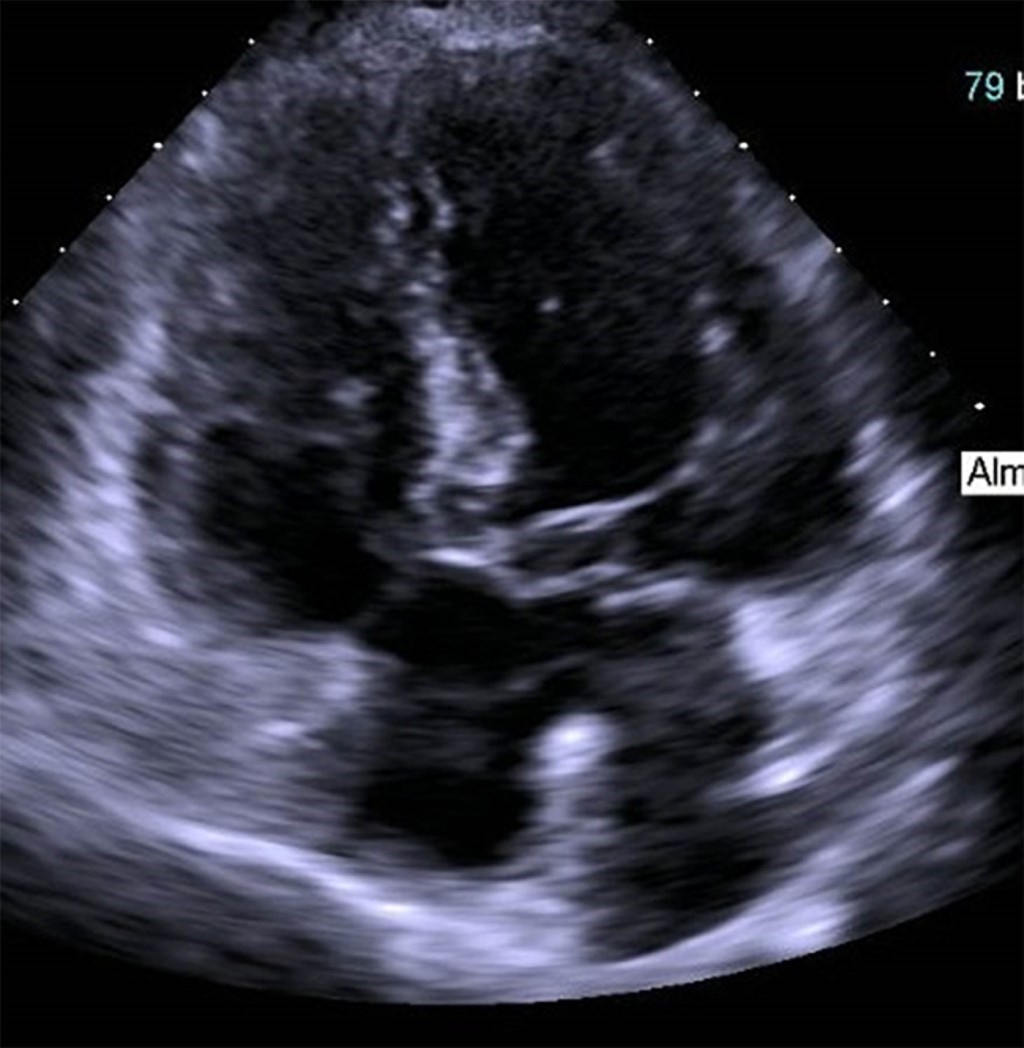

Figure 1